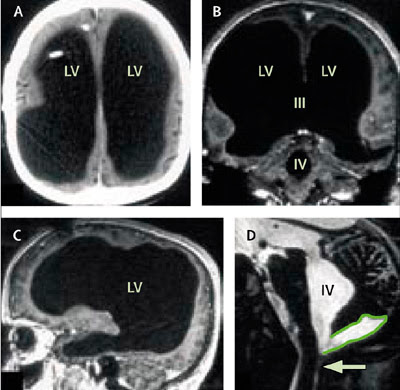

Eine Computertomografie und eine Kernspintomografie bei dem 44-Jährigen hätten «äußerst ungewöhnliche» Bilder erbracht. Das Gehirn des Mannes sei eigentlich nicht wirklich vorhanden. Dies sagte der Arzt Lionel Feuillet vom Marseiller Spital La Timone zu einem Bericht in der jüngsten Ausgabe der Fachzeitschrift «Lancet».

Gemäß neuropsychologischen Untersuchungen habe der Mann einen Intelligenzquotienten (IQ) von ca. 75. Der Durchschnitt liegt heute bei ca. 100. Bei den Untersuchungen habe sich gezeigt, dass die üblichen Hohlräume im Gehirn sich bei dem Mann massiv ausgedehnt hätten, sagte Feuillet. Trotz allem ist er nahezu normal entwickelt und hat sich ein soziales Netz aufgebaut.

«Das Gehirn selbst, also die graue und weiße Nervenmasse, war völlig -wie eine Schale- an den Rand des Schädels gedrückt.» Der zweifache Vater habe trotzdem ein normales Leben geführt.

Erkennbar sind die mit Flüssigkeit gefüllten Ventrikel (schwarze Fläche, Bild oben). Normalerweise weist die Gehirnrinde eine Dicke von etwa 4 Zentimetern auf, bei ihm war sie jedoch auf die Dicke eines Papierblattes zusammengeschrumpft. Dr. Lorber schätzte, dass das gesamte Gehirn des Mannes nur etwa 100 Gramm wog. Ein normales Gehirn eines Erwachsenen wiegt zum Vergleich etwa 1,3 Kilogramm, also 13-mal soviel. Der Student litt unter einem Wasserkopf, einer Krankheit, bei der die Gehirn-Rückenmark-Flüssigkeit anstatt um das Gehirn zu zirkulieren und anschließend in den Blutstrom überzugehen, im Inneren aufgestaut wird.